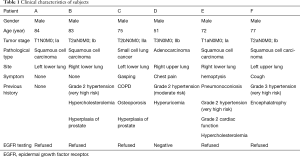

Six male patients with early lung cancer who were admitted to our hospital between June 2012 and April 2015 were included. Their age ranged from 51 to 84 years (73.67±12.0 years on average). Four of them had squamous cell carcinoma,1 had adenocarcinoma, and 1 had small cell lung cancer. The authors are accountable for all aspects of the work in ensuring that questions related to the accuracy or integrity of any part of the work are appropriately investigated and resolved. This study was approved by the Ethics Committee of the Second Affiliated Hospital of Fujian Medical University (approval No. 2012-002). All procedures performed in this study involving human participants were in accordance with the Declaration of Helsinki (as revised in 2013). Informed consent was taken from all the patients.

The clinical characteristics are listed in Table 1.

(I) Reasons for non-surgical treatment in the 6 patients were the following: advanced age in one patient (patient A), advanced age and multiple underlying diseases in 4 patients (patient B, C, E and F), and personal unwillingness in one patient (patient D). (II) Time of enrollment was between June 2012 and November 2015, as shown in Figure 3. (III) In the pulmonary lesions treated with 125I radioactive particles, the longest tumor diameter was 6.04 cm, and the shortest diameter was 2.04 cm (3.79±1.37 cm on average). At each site, 20–55 particles were implanted, for a total of 226 particles. One patient received an implantation of 125I radioactive particles twice.